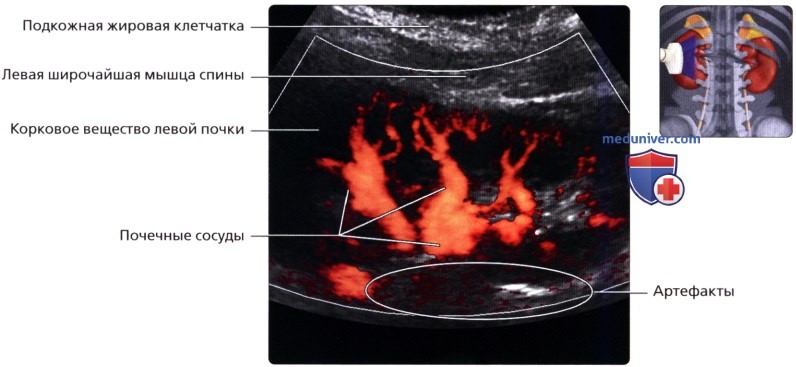

Неотъемлемой частью обследования почек стало ультразвуковое допплерографическое исследование, дающее возможность наблюдать за кровотоком в почечных сосудах. Делая УЗИ сосудов почек, можно установить на ранней стадии стеноз артерий, сбои в кровоснабжении, сосудистые сбои.

УЗДГ (УЗИ сосудов почек) выполняется в положении больного лежа на боку или сидя. Каких-то особенностей у этой процедуры нет. Врач также перемещает датчик по поверхности кожи пациента, внимательно изучая постоянно меняющиеся на мониторе изображения.

б) Лучевая анатомия почки:

1. Обзор:

• Забрюшинные структуры бобовидной формы с четким контуром, смещающиеся при дыхании

• Почечные артерии:

о Места отхождения лучше всего визуализируются при сканировании по срединной линии спереди

о Правую почечную артерию обычно можно проследить от места отхождения до почки

о Для визуализации левой почечной артерии часто требуется установить датчик на заднебоковой поверхности во фронтальной проекции

• Почечные вены:

о Лучше всего визуализируются при поперечном трансабдоминальном сканировании

о Также могут быть видны при сканировании в фронтальной плоскости с заднебоковой поверхности

Ультразвуковое исследование при заболеваниях сосудов почечного кровообращения

К этим заболеваниям относятся поражения почечной вены и артерий. Это могут быть сужения (стенозы), закупорка тромбом (тромбозы), а также нарушение целостности сосудов при травмах.